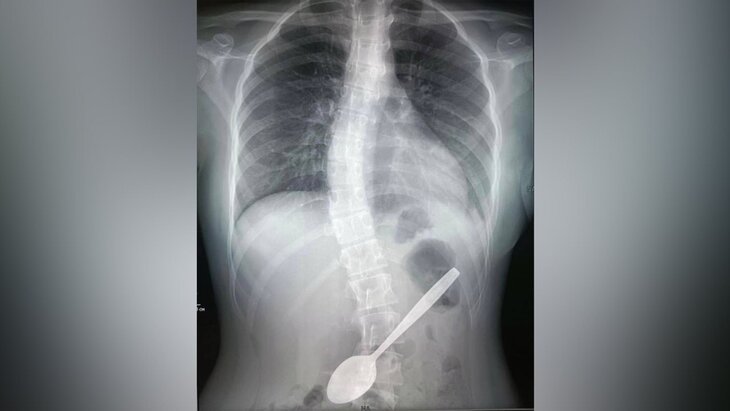

Врачи Детского клинического центра имени Л. М. Рошаля спасли 14-летнюю девочку, которая случайно проглотила 15-сантиметровую ложку. Об этом сообщает пресс-служба подмосковного Минздрава.

По данным министерства, школьница пыталась с помощью ложки вытащить кусок яблока, застрявший у нее в горле. Врачи после сделанного рентгена, который подтвердил наличие инородного тела в желудке, решили провести ей операцию.

Воспользовавшись видеоскопом, медики обнаружили, что ложка упиралась тонкой частью в стенку желудка, а широкой – уходила в луковицу двенадцатиперстной кишки. Инородный предмет был извлечен с помощью эндоскопической петли и щипцов, а также хирургического зажима.